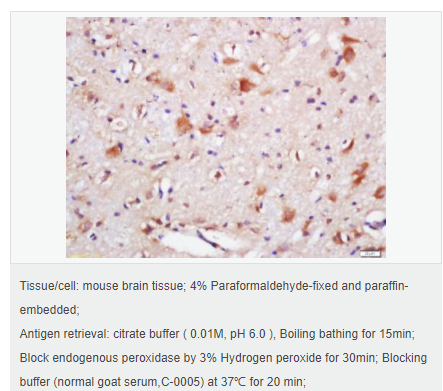

| 產(chǎn)品應(yīng)用 | ELISA=1:5000-10000 IHC-P=1:100-500 IHC-F=1:100-500 IF=1:100-500 (石蠟切片需做抗原修復(fù)) not yet tested in other applications. optimal dilutions/concentrations should be determined by the end user. |

| 免 疫 原 | KLH conjugated synthetic peptide derived from human SQSTM1/p62:51-150/440 |

| 產(chǎn)品介紹 | Adapter protein which binds ubiquitin and may regulate the activation of NFKB1 by TNF-alpha, nerve growth factor (NGF) and interleukin-1. May play a role in titin/TTN downstream signaling in muscle cells. May regulate signaling cascades through ubiquitination. Adapter that mediates the interaction between TRAF6 and CYLD (By similarity). May be involved in cell differentiation, apoptosis, immune response and regulation of K(+) channels. Function: Adapter protein which binds ubiquitin and may regulate the activation of NFKB1 by TNF-alpha, nerve growth factor (NGF) and interleukin-1. May play a role in titin/TTN downstream signaling in muscle cells. May regulate signaling cascades through ubiquitination. Adapter that mediates the interaction between TRAF6 and CYLD (By similarity). May be involved in cell differentiation, apoptosis, immune response and regulation of K(+) channels. Subunit: Cytoplasm. Late endosome. Nucleus. Endoplasmic reticulum. Note=Sarcomere. In cardiac muscles localizes to the sarcomeric band. Localizes to late endosomes. May also localize to the nucleus. Accumulates in neurofibrillary tangles and in Lewy bodies of neurons from individuals with Alzheimer and Parkinson disease respectively. Enriched in Rosenthal fibers of pilocytic astrocytoma. In liver cells, accumulates in Mallory bodies associated with alcoholic hepatitis, Wilson disease, indian childhood cirrhosis and in hyaline bodies associated with hepatocellular carcinoma. Colocalizes with TRIM13 in the perinuclear endoplasmic reticulum. Subcellular Location: Cytoplasm. Late endosome. Nucleus. Sarcomere (By similarity). In cardiac muscles localizes to the sarcomeric band (By similarity). Localizes to late endosomes. May also localize to the nucleus. Accumulates in neurofibrillary tangles and in Lewy bodies of neurons from individuals with Alzheimer and Parkinson disease respectively. Enriched in Rosenthal fibers of pilocytic astrocytoma. In liver cells, accumulates in Mallory bodies associated with alcoholic hepatitis, Wilson disease, indian childhood cirrhosis and in hyaline bodies associated with hepatocellular carcinoma. Tissue Specificity: Ubiquitously expressed. Post-translational modifications: Phosphorylated. May be phosphorylated by PRKCZ (By similarity). Phosphorylated in vitro by TTN. DISEASE: Defects in SQSTM1 are a cause of Paget disease of bone (PDB) [MIM:602080]. PDB is a metabolic bone disease affecting the axial skeleton and characterized by focal areas of increased and disorganized bone turn-over due to activated osteoclasts. Manifestations of the disease include bone pain, deformity, pathological fractures, deafness, neurological complications and increased risk of osteosarcoma. PDB is a chronic disease affecting 2 to 3% of the population above the age of 40 years. Similarity: Contains 1 OPR domain. Contains 1 UBA domain. Contains 1 ZZ-type zinc finger. SWISS: Q13501 Gene ID: 8878 Database links: Entrez Gene: 8878 Human Entrez Gene: 18412 Mouse Omim: 601530 Human SwissProt: Q13501 Human SwissProt: Q64337 Mouse Unigene: 709030 Human Unigene: 40828 Mouse Unigene: 107103 Rat Important Note: This product as supplied is intended for research use only, not for use in human, therapeutic or diagnostic applications. |